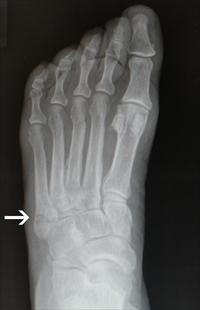

(Note: post contains X-rays of feet — I don’t know if anyone else out there has lifelong Issues with foot bones, but we thought we should give a heads-up just in case.)

Six weeks ago yesterday, I broke my foot. Suffice to say, it was a learning experience, and the main lesson was, breaking your foot is terrible, don’t do it.

- then the doctor goes, “Okay, you can take that off now!” and suddenly you’re back to hobbling around with a walking stick

- I think my foot has forgotten how to be a foot